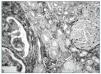

En diciembre de 2005 ingresó por anuria, edemas y dolor infraabdominal, mostrando deterioro agudo de Creatinina (3,5 mg/dl), proteinuria de 4,2 g/24 h y hematuria de 100 h/c, precisando de hemodiálisis temprana. Se obtuvo una nueva biopsia informada como esclerosis sobre el 50% de los glomérulos presentando la mayoría de los restantes una GN extracapilar con semilunas epiteliales, asociada a GM, con moderada fibrosis intersticial. En los estudios de imagen se encontraron imágenes sugestivas de EQA, destacando un nódulo sólido de 2,5 cm en polo superior del riñón derecho, con sospecha de malignidad, por el que sufrió nefrectomía.

La pieza mostraba múltiples quistes y el nódulo, de 3 cm, era de coloración verde grisácea. Microscópicamente, el parénquima renal estaba muy desestructurado, con esclerosis, semilunas y afectación tubulointersticial intensa, mostrando adenomas papilares y tubulopapilares, constituyendo ocasionalmente un Microcarcinoma Papilar y abundantes cambios oncocíticos, formando agregados nodulares intersticiales. El nódulo mayor correspondía a un Oncocitoma convencional.

Figura 1.